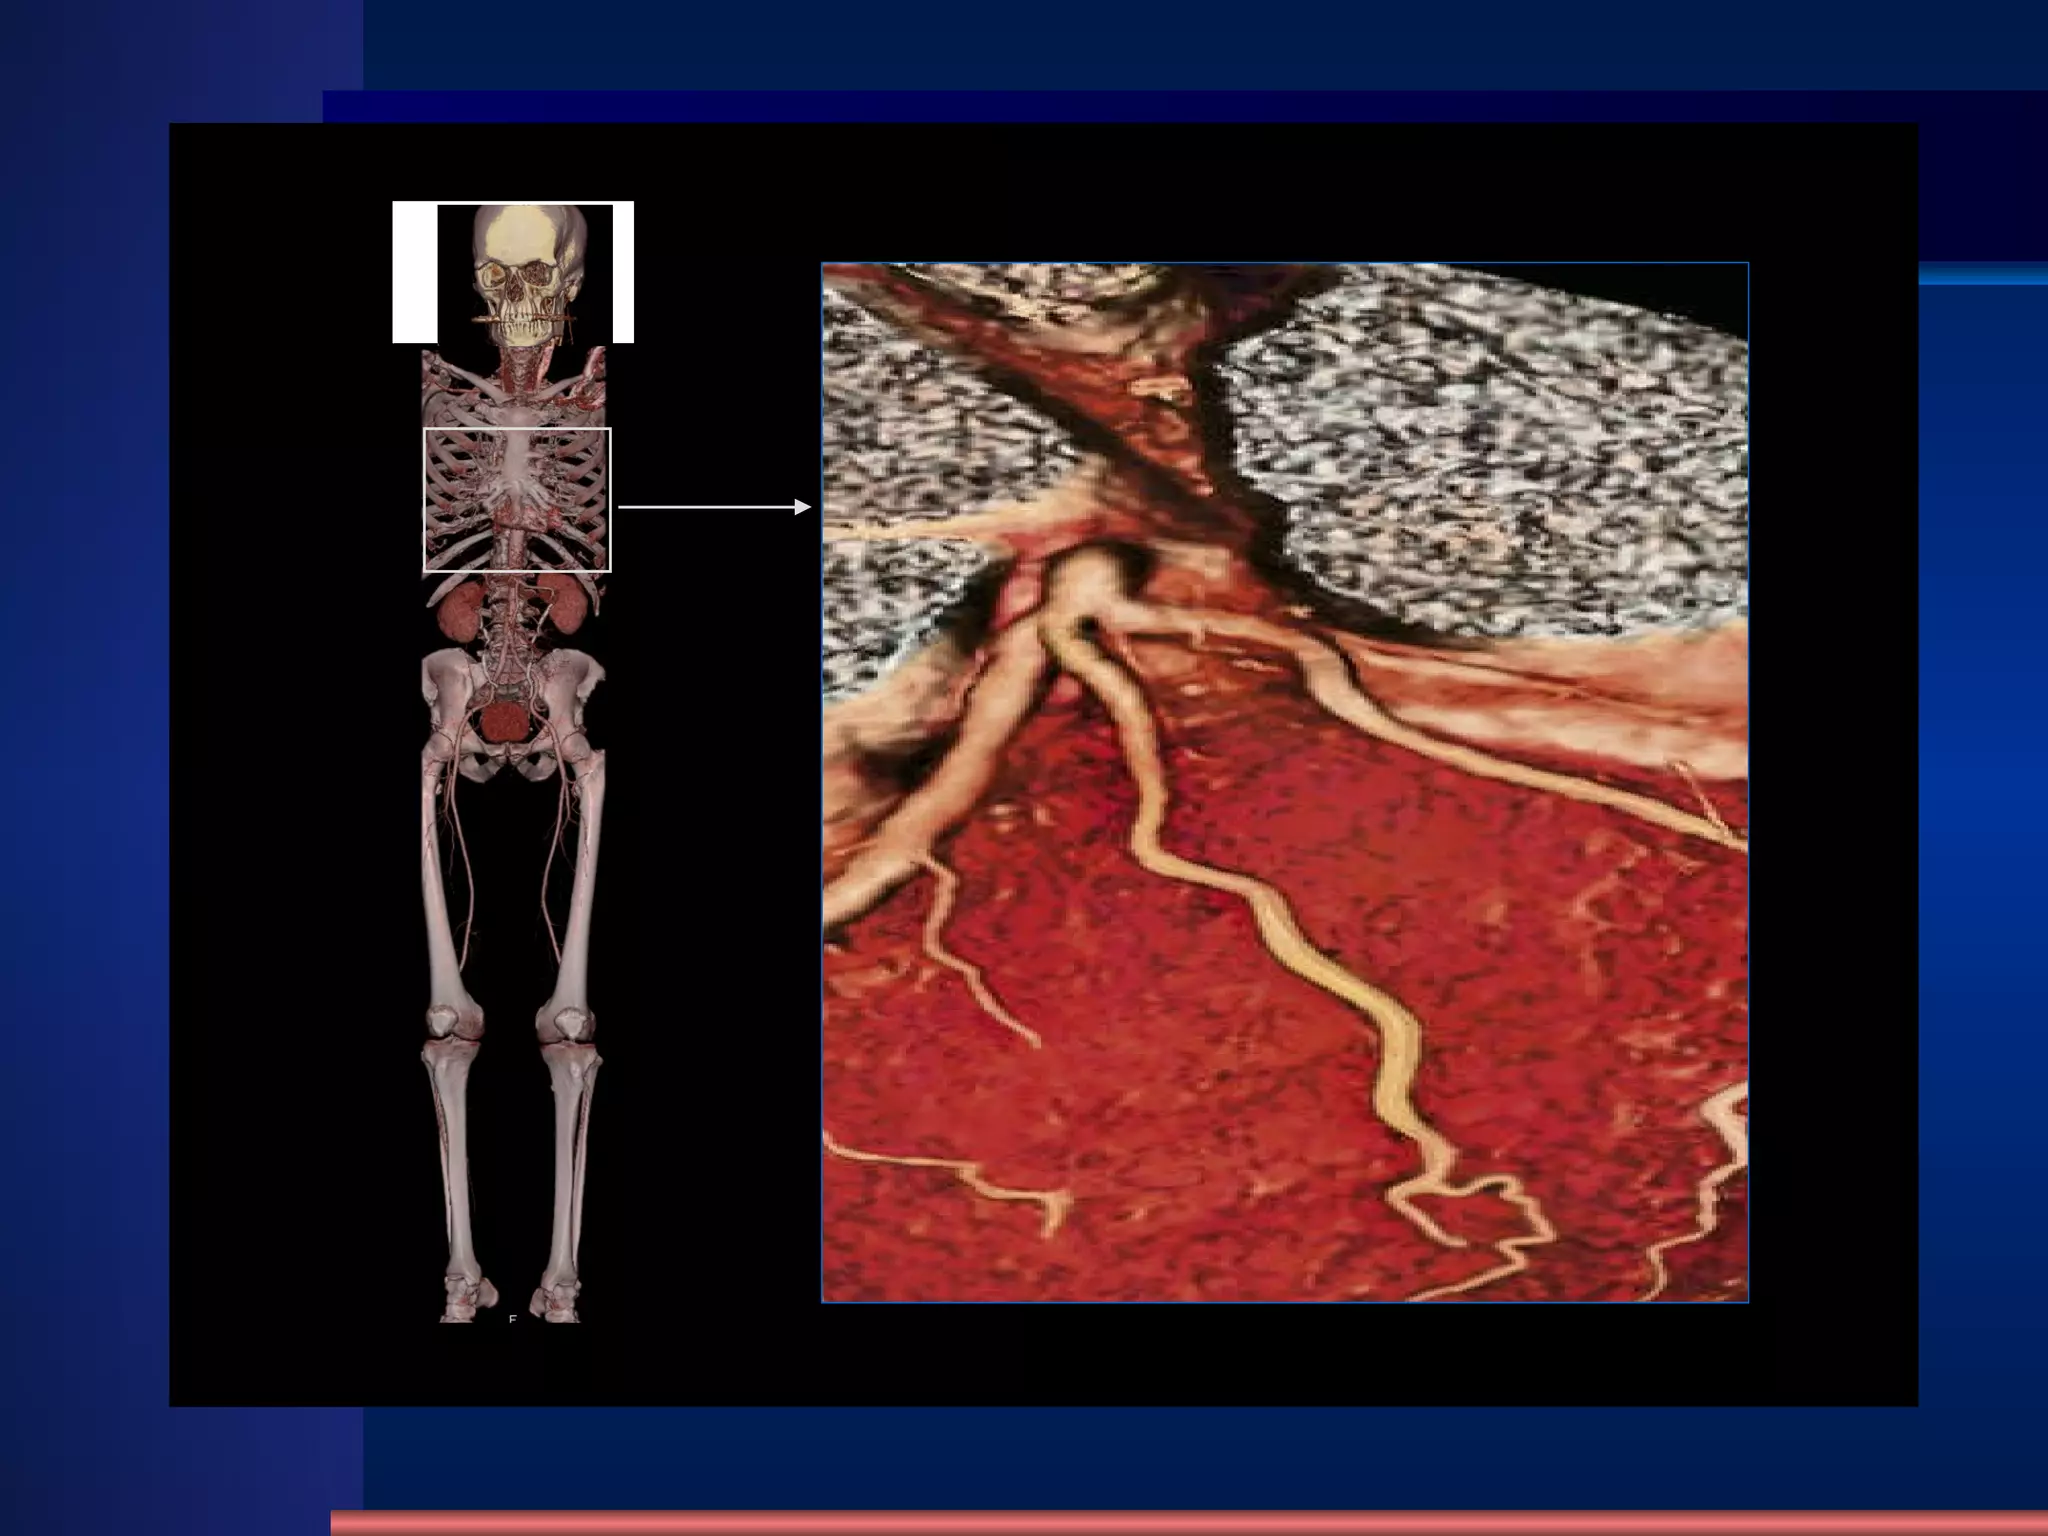

VRT Recon. Normal Coronary artery CTA

Coronary artery CTA MIP With Contrast Medium

前降支和旋支 前降支和对角支 前降支和旋支 心底部冠脉供血 正常冠脉 MIP 重建

前降支和旋支 前降支和对角支 前降支和旋支心底部冠脉供血 正常冠脉 MIP 重建